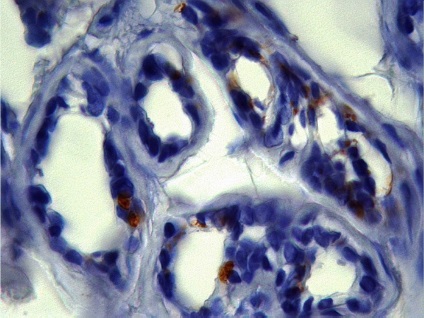

Ábra. Immunhisztokémia 11: CD-31 expressziója a vaszkuláris endotéliumon, a bőrben a haemangiomatosis

Következtetés (patológus MD Karev VE): egy jóindulatú daganat tömegének faggyúmirigy; haemangiomatosis bőrben, cutan vasculitis (gyulladásos elváltozások érfalak).